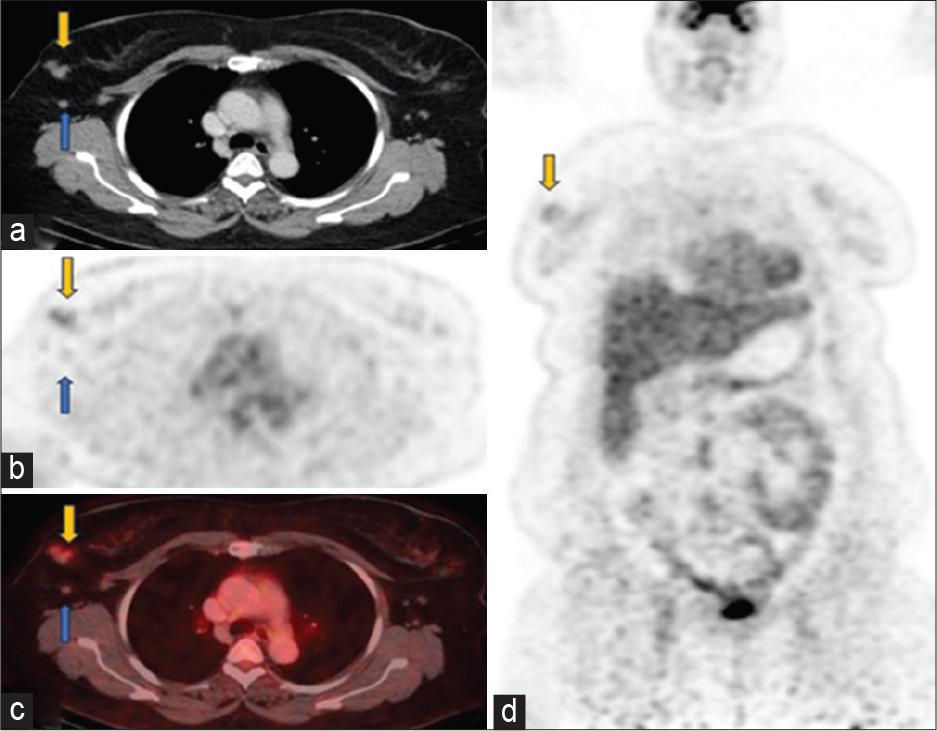

Follow-up scan June 2023 (a) axial computed tomography (CT), (b) positron emission tomography only, (c) fused positron emission tomography-CT images through the chest showed significant interval decrease in size and metabolic activity of right breast mgass (yellow arrows) with faint uptake (SUV 2.6). Right axillary lymphadenopathy has also significantly reduced leaving behind residual non-avid (SUV 1.2) subcentimeter nodes (blue arrows). (d) Coronal positron emission tomography-only images showed a faintly avid residual tumor in the right breast